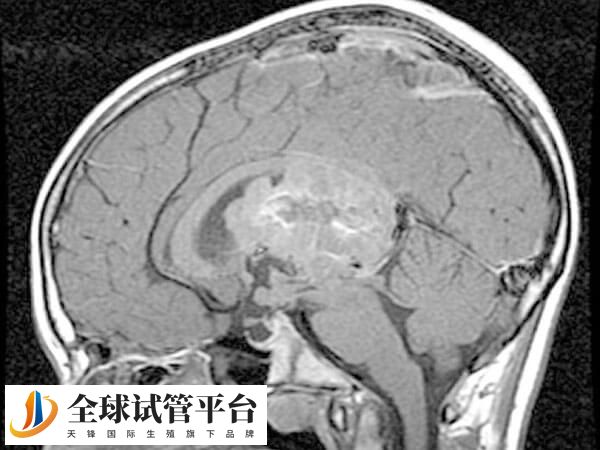

三叉神经鞘瘤(Trigeminal Schwannoma)是起源于三叉神经雪旺细胞的良性肿瘤,占颅内肿瘤的0.07%-0.36%。

这类肿瘤虽然生长缓慢,但位置复杂,常累及中颅窝、后颅窝或跨颅窝生长,导致多种神经功能障碍。

不过要注意的是,三叉神经鞘瘤的确切病因尚不完全清楚,但绝大数也是异常细胞增殖所引起的异常生长。因此手术切除是目前三叉神经鞘瘤的主要治疗方法,手术方法取决于肿瘤类型、发生位置、影像学特点和其他相关因素(包括病人的整体健康状况、总体的手术难度及风险)。